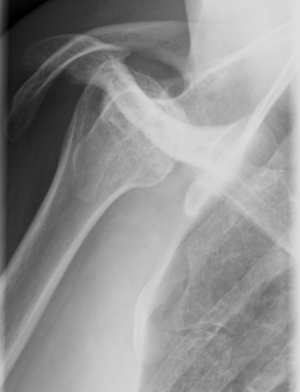

Axillary view

Acute

As a Bernageau view is difficult to obtain in acute cases because of severe pain, Velpeau axillary views is an alternative (Figure 19).[19]

Recurrent/Congenital/Acquired

Bernageau view is the best to demonstrate posterior glenoid rim deficiency posterior subluxation and associated bone loss.